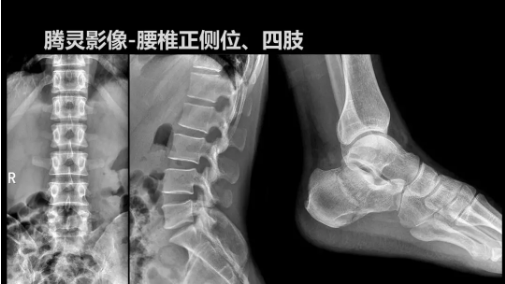

2019年10月19日,82屆秋季CMEF于青島世博城國際展覽中心如期舉辦,國內(nèi)動態(tài)DR領(lǐng)域的佼佼者安健科技攜新品——“騰靈”多功能診斷專用動態(tài)DR亮相展會現(xiàn)場。

“騰靈”是安健科技的第四代動態(tài)DR產(chǎn)品,可實現(xiàn)全科室應(yīng)用。如各類常規(guī)的X線檢查、消化道檢查、骨科檢查、婦科、兒科檢查等。此外,安健科技為“騰靈”在真正意義上實現(xiàn)多科室、多功能診斷進(jìn)行了多項針對性設(shè)計。

相較前代產(chǎn)品,“騰靈”在圖像質(zhì)量方面得到了全面升級,“騰靈”采用17*17非晶硅平板探測器設(shè)計,采集矩陣達(dá)3072*3072,動態(tài)范圍達(dá)16bit,為成像提供超大視野的同時保證成像質(zhì)量,此外,該款機(jī)型可根據(jù)醫(yī)療機(jī)構(gòu)的差異化需求而選配不同的動態(tài)平板探測器,以此來適應(yīng)不同階層用戶所需。